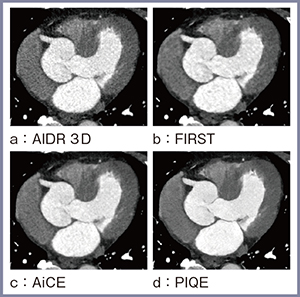

4.臨床画像

図4は70歳代,男性の冠動脈CT画像である。身長177cm,体重82kgとやや体格の大きい患者で,少し線量不足の撮影となったため,AIDR 3D(図4 a)やFIRST(b)ではノイズが多くなった。AiCE(図4 c)を用いることでノイズを良好に抑制することができるが,PIQE(d)ではさらにしっかりとノイズを抑制でき,かつ空間分解能も高い画像を得られている。

同症例のCPR画像でソフトプラークによる約50%狭窄がある部分を拡大すると,PIQEではほかの再構成法と比較して,内腔とプラークの境界が明瞭に描出されていることがわかる(図5)。また,右側に分枝が確認できるが,PIQEでは分枝からさらに分岐する細い血管(←)も描出されており,PIQEが微細血管の描出においても有用であることがわかる。

図4 70歳代,男性(177cm/82kg)の

冠動脈CT画像